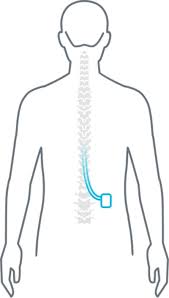

Stabilizacja dodatkowa (opcjonalna)

PSF (posterior spinal fixation):

- przy niestabilności,

- przy kręgozmyku,

- przy wielopoziomowych zmianach.